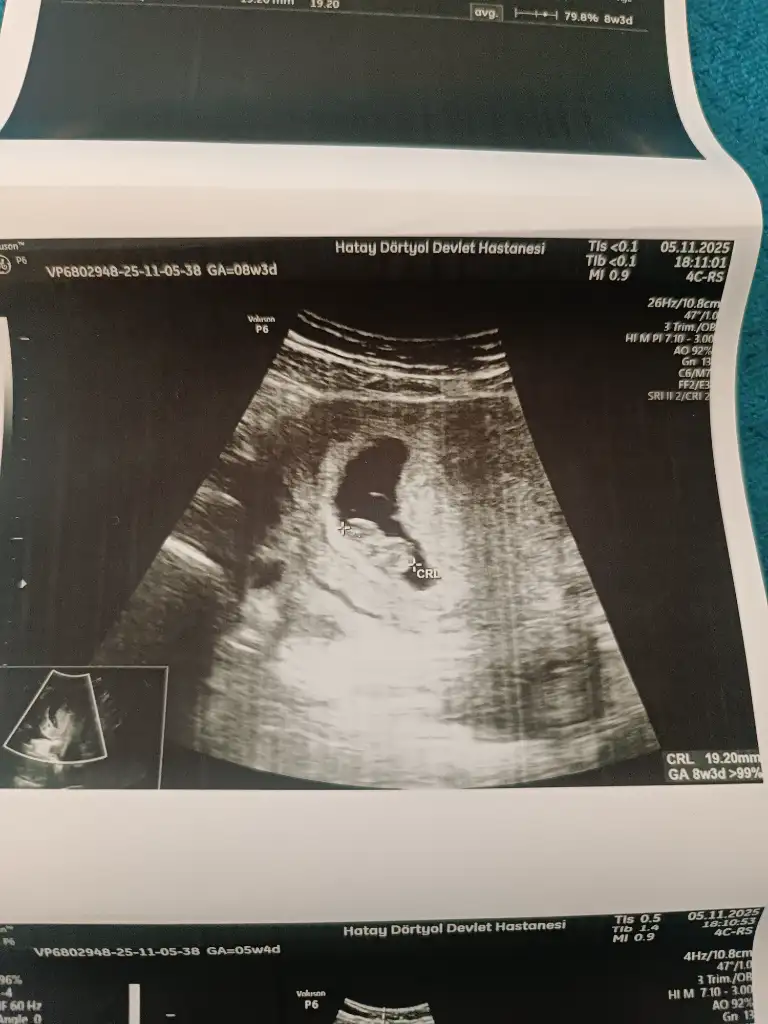

Evet erkek gibi. Yuvarlak olursa kız uzun oval fasulye olursa erkek diyorlar.Bak bakalımultrason görüntüsü 8+3

Yuvarlak görünüyor kız gibi sanki. Burdakilerden yola çıkarak söyliyorumKız tahmin edebilen varsa aramızda bana da bakınterzi kendi söküğünü dikemezmiş ben ayırt edemedim keseden kız mı erkek mi diye

Yuvarlak kız gibi duruyor